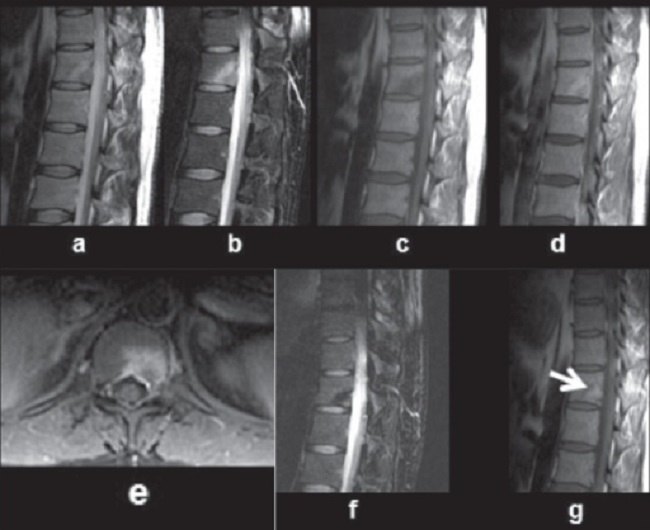

– Pemeriksaan radiologi pada tulang belakang, yaitu dengan X-ray, CT Scan (Computed Tomography Scan), MRI (Magnetic Resonance Imaging), USG, pemeriksaan PET, dan Bone Scan